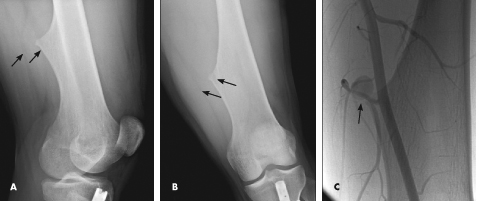

Plain radiographs of the knee are shown.

Along with mild soft tissue swelling in the distal thigh, the radiographs show an eccentric cortical outgrowth from the distal femur, directed away from the joint (A and B). The rod and nail present in the proximal tibia is related to a prior fracture.

The image findings are classic for osteochondroma. This cartilage-capped bony projection may arise from the external surface of any bone of cartilaginous origin. However, osteochondromas most commonly occur in the long bones. Similar to the physeal growth plate, an osteochondroma ceases to grow at puberty; cartilage decreases in thickness and undergoes ossification.

This patient underwent further evaluation with ultrasonography of the left thigh, which showed a pseudoaneurysm of the superficial femoral artery. This finding explained the acute onset of pain. A conventional angiogram confirmed the ultrasonography findings and showed the pseudoaneurysm coming off a branch vessel of the distal superficial femoral artery (C). Coil embolization of the pseudoaneurysm was performed.